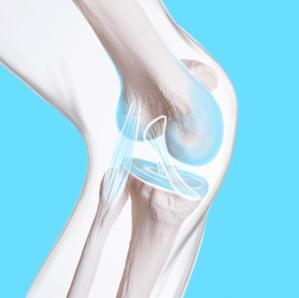

Gesundheit

Wer sich regelmässig moderat bewegt, stärkt den Knorpel im Knie und beugt so Ar throse vor.

Tanzen, laufen, hüpfen: Bei allem spielt das Knie eine zentrale Rolle. Wie du ihm Sorge trägst.

Was genau leistet das Knie?

Wenn wir gehen, tanzen oder etwas vom Boden aufheben, ist das Knie der Dreh- und Angelpunkt. Es ist ein sogenanntes Scharniergelenk. Du kannst es beugen, strecken, aber auch seitlich bewegen und drehen. Das Knie verbindet die beiden längsten Knochen im Körper: den Oberschenkelknochen und den Schienbeinknochen. Neben der Schulter ist das Knie das komplexeste und instabilste Gelenk unseres Körpers und häufig von Verletzungen betroffen.

Wie schütze ich mein Knie?

Kräftige Muskeln schonen das Gelenk und verhindern so Verletzungen wie Bänderrisse und kleine Blutergüsse, die später zu Knorpelschäden und Arthrose führen können. Die Knochendichte wird durch Muskeltraining ebenfalls gefördert. Untrainierte sollten die Beinmuskulatur vor allem vor grösseren Belastungen – zum Beispiel vor langen Wanderungen mit steilen Abstiegen – stärken. Dafür gibts einfache Übungen wie Treppensteigen. Dabei sollte man sich nicht mit dem hinteren Fuss abstossen, wie man das

Fortsetzung von Seite 43

im Alltag macht, sondern sich rein mit der Kraft des vorderen Beins auf die nächste Stufe heben.

Gibt es No-Gos im Alltag?

Schlecht sind Positionen, bei denen die Knie stark gepresst werden – etwa ein extremer Schneidersitz. Damit üben wir Druck auf den inneren Gelenkspalt und damit auf den Meniskus aus. Auch länger knien und in die Hocke gehen ist nicht gut. Dadurch wird die Kniescheibe gegen den Oberschenkel gedrückt, der Knochen wird dadurch stark belastet und der Knorpel leidet.

Sind O- oder X-Beine schlecht fürs Knie?

Ja. Wer extreme X- oder O-Beine hat, muss eher mit Arthrose rechnen. Der einseitige Druck belastet den Knorpel besonders. Das Knie mag eine gleichmässige Lastenverteilung. Eine starke Ungleichheit sollte allenfalls durch eine OP korrigiert werden.

Was macht Bewegung mit dem Knie?

Durch regelmässige moderate Bewegung wird der Knorpel im Knie gestärkt. Er ernährt sich aus der Gelenkflüssigkeit. Bewegung fördert diesen Vorgang. Auch Menschen, die bereits unter Arthrose

Das Knie verbindet die beiden längsten Knochen im Körper: den Oberschenkel- und den Schienbeinknochen.

Neben der Schulter ist das Knie das komplexeste und instabilste Gelenk und häufig von Verletzungen betroffen.

Gibts in der Migros leiden, können auf diese Weise ihre Schmerzen verringern. Empfehlenswert sind Nordic Walking, Wandern in nicht zu steilem Gelände, Radfahren und Schwimmen. Joggen dagegen fordert das Knie stark, denn dabei lastet das mehrfache Körpergewicht auf den Gelenkflächen. Wer bereits mit Knieproblemen zu kämpfen hat, sollte darauf verzichten.